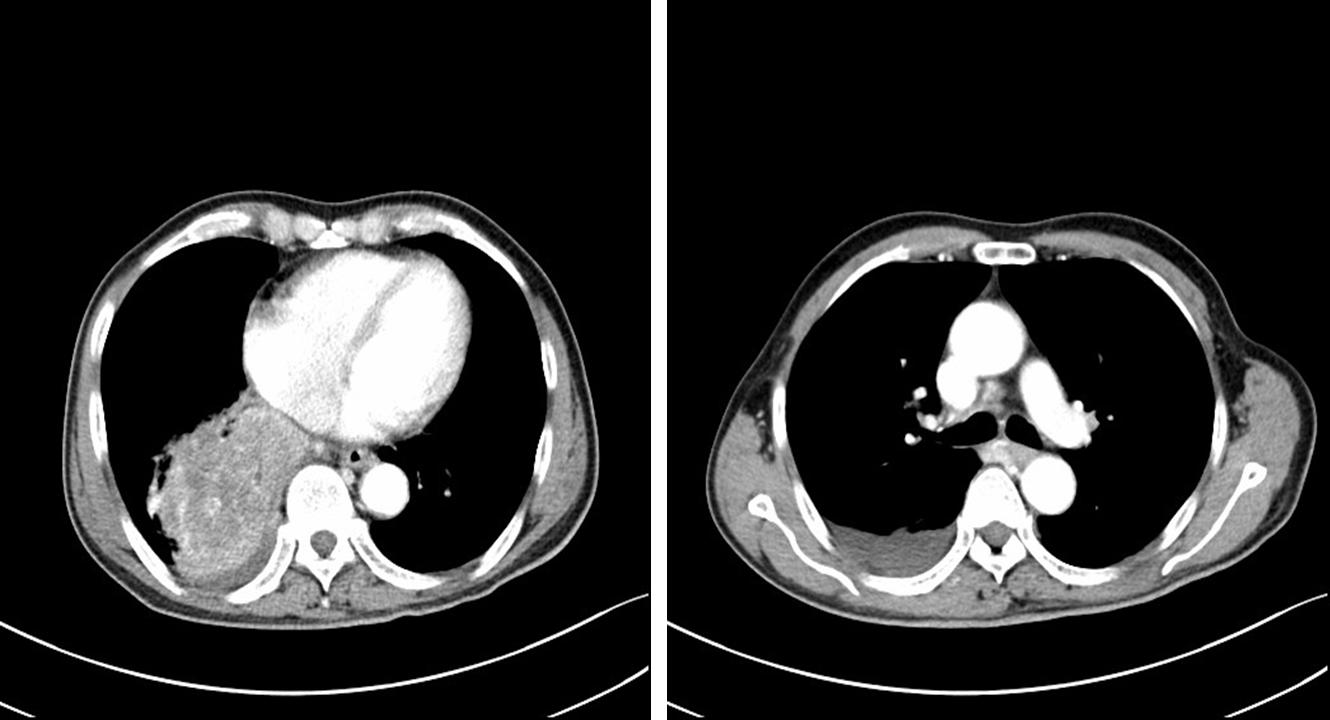

朱某某,男性,69岁。2018年9月因咳嗽、痰中带血伴胸闷不适,检查发现右下肺占位就诊。病理经皮肺穿刺示:鳞癌。诊断为:右下肺鳞癌,临床分期T4NxM0 Ⅲ期,PS评分1分,基因状态未知。

图1. 2018年9月21日首诊CT